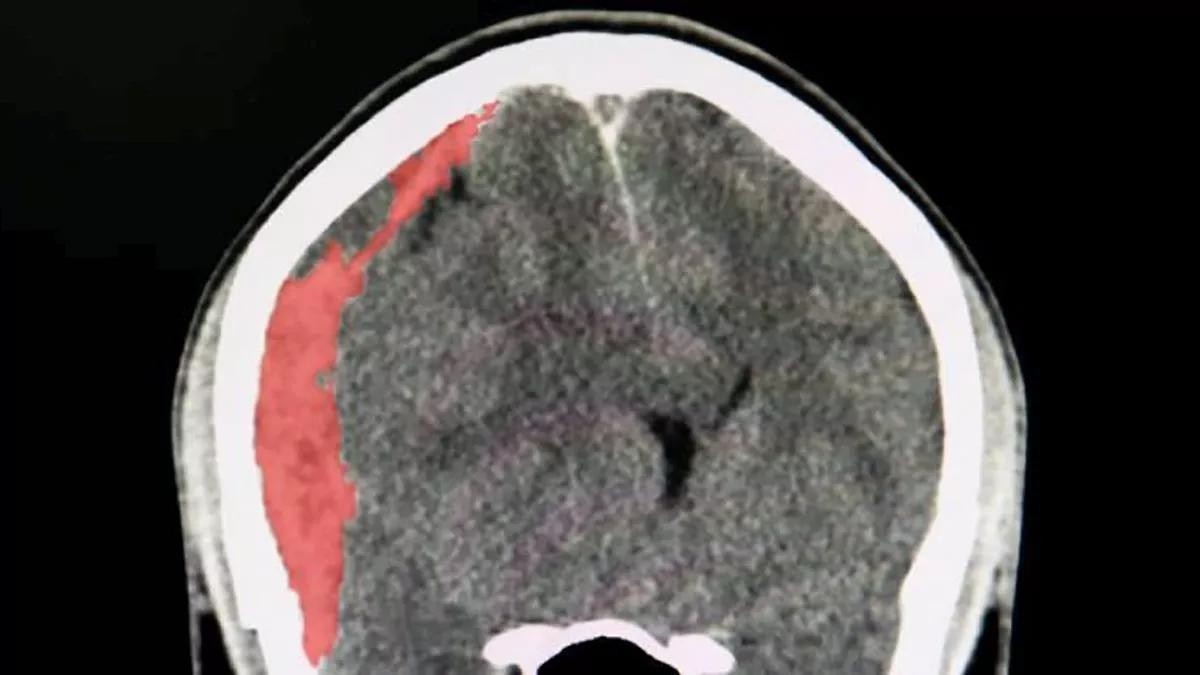

Un enemigo silencioso, un hematoma subdural, fue quien se llevó la vida del maestro según información proporcionada por su estudio el 7 de marzo (8 de marzo en Japón), poniendo de relieve la importancia de conocer esta condición médica, sus riesgos y síntomas. Aquí te dejamos más detalles de esta grave afección.

Un hematoma subdural es una acumulación de sangre entre la cubierta del cerebro (duramadre) y la superficie del mismo. Esta acumulación genera presión sobre el tejido cerebral, lo que puede derivar en un traumatismo craneal y, en algunos casos, la muerte.

El tamaño del hematoma, el ritmo de aumento de la presión craneal y la rapidez en recibir atención médica son claves para el pronóstico del paciente. Un diagnóstico temprano y un tratamiento adecuado, que generalmente incluye una cirugía para drenar la sangre acumulada y disminuir la presión, pueden reducir considerablemente la mortalidad y las posibles secuelas neurológicas.